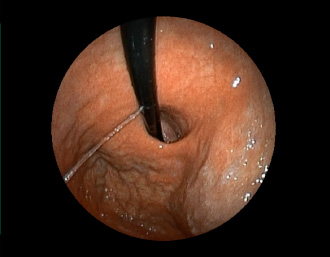

症例9:食道裂孔ヘルニア(84才女性)

胃からの反転観察像で、EGJおよび胃粘膜が食道側への滑脱を認める。

通常画像